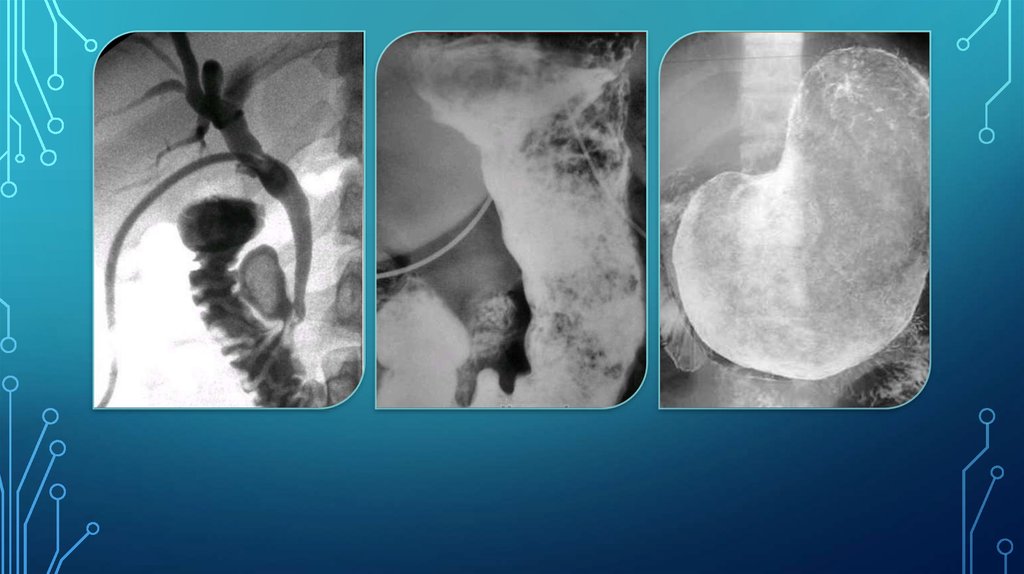

13. Безоар толстой кишки

БЕЗОАР ТОЛСТОЙ КИШКИ

14.

15.